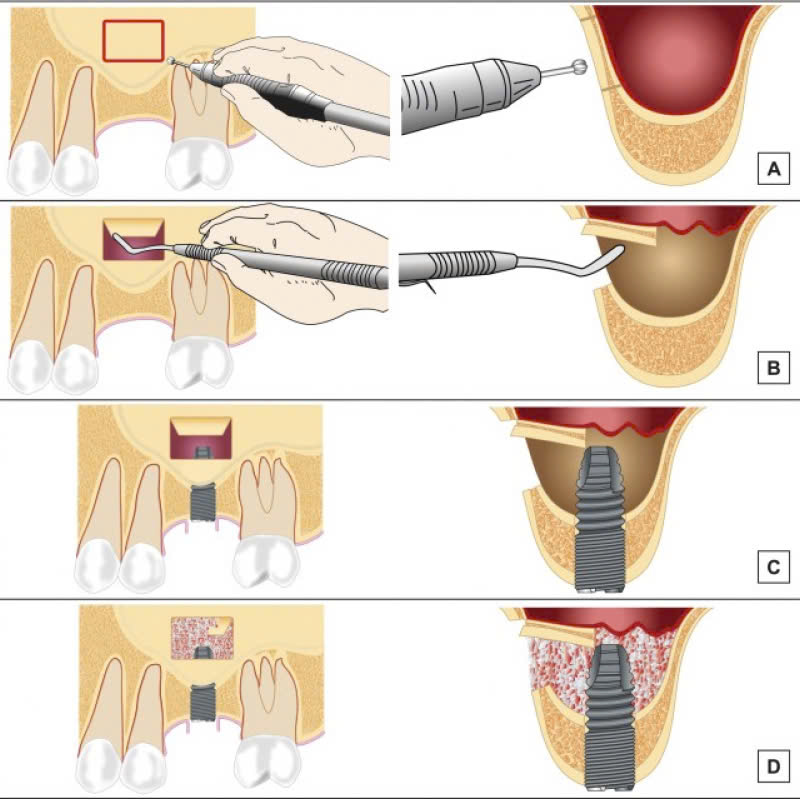

Quy trình thực hiện nâng xoang kín bao gồm các bước sau:

Bước 1: Thăm khám và chụp CT

Đây là bước quan trọng đầu tiên, bác sĩ sẽ tiến hành khám và chụp CT để đánh giá tình trạng xoang hàm của khách hàng. Từ đó, họ sẽ lên kế hoạch điều trị phù hợp.

Bước 2: Sát khuẩn và gây tê

Trước khi tiến hành phẫu thuật, vùng cần can thiệp sẽ được sát khuẩn cẩn thận và gây tê cục bộ để đảm bảo an toàn và không gây đau cho khách hàng.

Bước 3: Mở đường rạch

Bác sĩ sẽ mở một đường rạch nhỏ, khoảng 3-6mm phía dưới chân răng, để tiếp cận vùng xoang hàm.

Bước 4: Nâng màng xoang

Sau khi mở đường rạch, bác sĩ sẽ cẩn thận nâng màng xoang lên cao.

Bước 5: Ghép xương

Tiếp theo, xương được đưa vào lấp đầy khoảng trống ở vùng xoang hàm.

Bước 6: Cấy implant và khâu vạt nướu

Sau khi ghép xương, bác sĩ sẽ tiến hành cấy trụ Implant và khâu vạt nướu lại.

Bước 7: Chụp phim kiểm tra

Cuối cùng, bác sĩ sẽ chụp phim để kiểm tra tình trạng sau phẫu thuật.

Cả quy trình diễn ra trong vòng 1-2 giờ, tùy thuộc vào từng trường hợp cụ thể. Sau đó, khách hàng cần được theo dõi và chăm sóc cẩn thận để đảm bảo quá trình hồi phục diễn ra tốt đẹp.